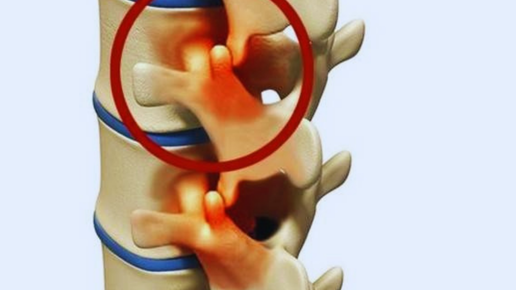

Что такое костные шпоры? Когда нужно лечить

Сделали рентгеновский снимок грудной клетки, обнаружили наросты на позвонках, остеофиты( костные шпоры). А нужно ли их лечить? Костные шпоры (остеофиты) представляют собой наросты, которые образуются поверх нормальной кости. Остеофиты часто образуются там, где кости встречаются друг с другом — в суставах. Они также могут образовываться на костях позвоночника, локтевых сгибов, плеч, бедер, коленей, на нижней или задней поверхности пяточной кости. Основной причиной костных шпор является поражение суставов, связанное с остеоартритом...